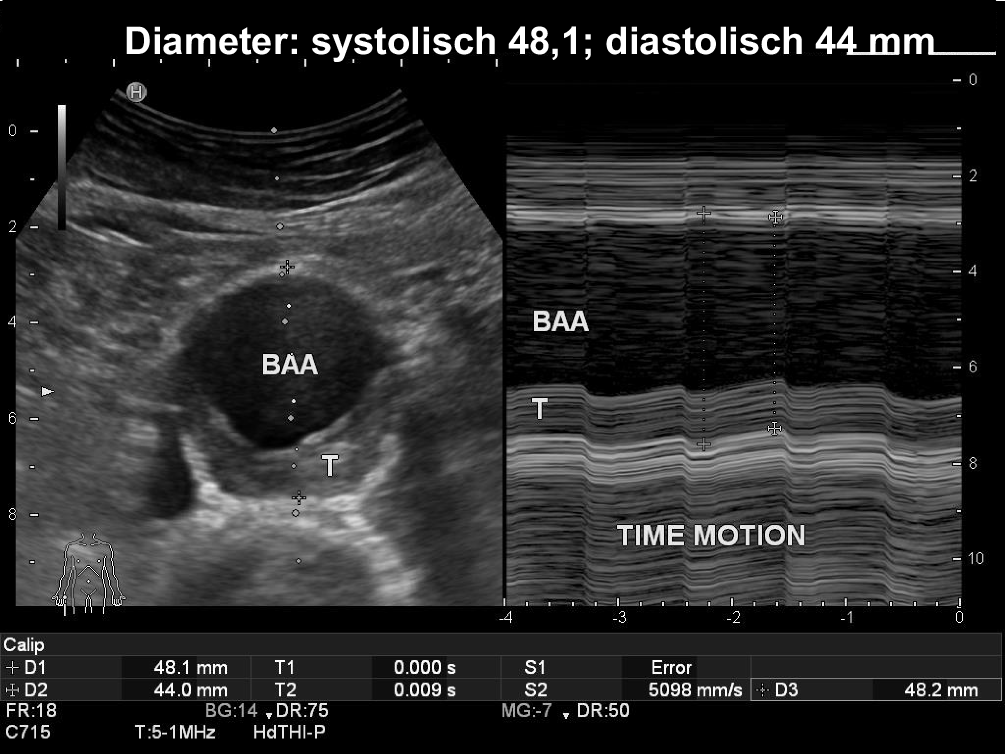

Abb. 4

Systolisch-diastolische Durchmesserschwankung von systolisch 48 mm auf diastolisch 44 mm im Time-motion-Modus (LELE[„leading-to-leading edge“]-Methode) dargestellt: Im B‑Bild-Querschnitt (rechts) ist der Durchmesser mit 48 mm zufällig in der Systole dargestellt (vgl. Videoclip 2)

Diameterschwankung in Abhängigkeit vom Herzzyklus

Bei einer exakten Durchmesserbestimmung ist zu bedenken, dass sowohl bei der unauffälligen Aorta als auch beim Aortenaneurysma systolisch-diastolische Durchmesserschwankungen bis zu 5 mm möglich sind (Abb. 4). Kaum eine sonographische Studie geht auf die herzzyklusabhängigen Messwerte ein [34], und in CT-Aufnahmen zu einem zufälligen Zeitpunkt werden diese Schwankungen gar nicht berücksichtigt. Lediglich in wenigen CTA- und MRA-Studien wurde mittels eines speziellen Tracking-Systems insbesondere in Vorbereitungs- oder Verlaufsuntersuchungen bei EVAR über herzzyklusabhängige Schwankungen von 1–5 mm berichtet [35, 36, 37, 38, 39]. Dabei wurde jedoch meist nur der Aneurysmahals für die richtige Wahl von Stentgraftgröße und -design und für die Risikoabwägung einer Stentmigration beurteilt [40]. Eine eigene sonographische Untersuchung zeigt bei 46 AAA am maximalen Aneurysmadurchmesser eine mittlere systolisch-diastolische Schwankung von 2,3 mm (1,1–4,6 mm; [32]). Eine mittlere Differenz von 1,94 mm zwischen Systole und Diastole wurde in einer Auswertung von sonographischen Videoclips festgestellt [34]. Differenzen sowohl in der Verlaufskontrolle als auch im Methodenvergleich lassen sich dadurch erklären. Als hilfreich wird hier eine EKG(Elektrokardiographie)-getriggerte Messung angesehen [41]. Diese ist jedoch weder im Screening noch bei routinemäßigen AAA-Verlaufskontrollen zu fordern oder durchführbar. Bei einer deutlichen Diameterzunahme um mehr als 3 mm in der halbjährlichen Verlaufsuntersuchung sollte jedoch die bei verschiedenen AAA sehr unterschiedliche pulsatile Schwankung in einer systolisch-diastolischen Vergleichsmessung bestimmt werden, die am einfachsten und zuverlässigsten im Time-motion-Modus an der Stelle mit breitestem AAA-Durchmesser in orthogonaler Messebene durchzuführen ist (Abb. 4; Videoclip 2). Bei starker Pulsatilität muss die Diameterzunahme relativiert werden, und statt einer verfrühten Operationsindikation muss diese engmaschig systolisch-diastolisch verlaufskontrolliert werden.